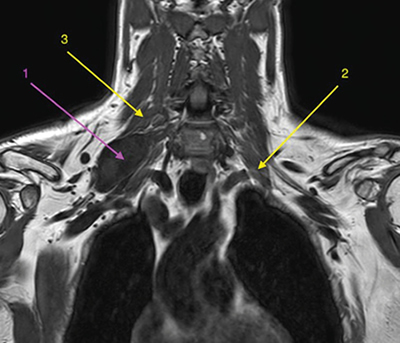

Con la orientación diagnóstica inicial de schwannoma de plexo braquial derecho con escasa repercusión clínica, se decidió actitud expectante. Se instauró tratamiento analgésico de primer escalón y ansiólisis a demanda para dormir. El paciente era reticente al tratamiento neuromodulador debido a sus efectos secundarios. Seis meses después, tras una nueva RM de control, se observó un discreto crecimiento de la lesión con probable efecto compresivo por los músculos escalenos anterior y medio (Figuras 1 y 2). Se indicó una infiltración diagnóstico-terapéutica con toxina botulínica tipo A (Botox®) ecodirigida. Las crisis de dolor eran más frecuentes y de más minutos de duración y empezaban a afectar su calidad de vida. EVA 2-3 en reposo, 8-9/10 en las crisis.

Fig. 1. RM coronal en T1. 1. Schwannoma de plexo braquial derecho. 2. Músculo escaleno anterior izquierdo, para mostrar su ubicación relativa al plexo braquial ipsilateral, dado que en el lado derecho no se identifica claramente. 3. Músculo escaleno medio derecho